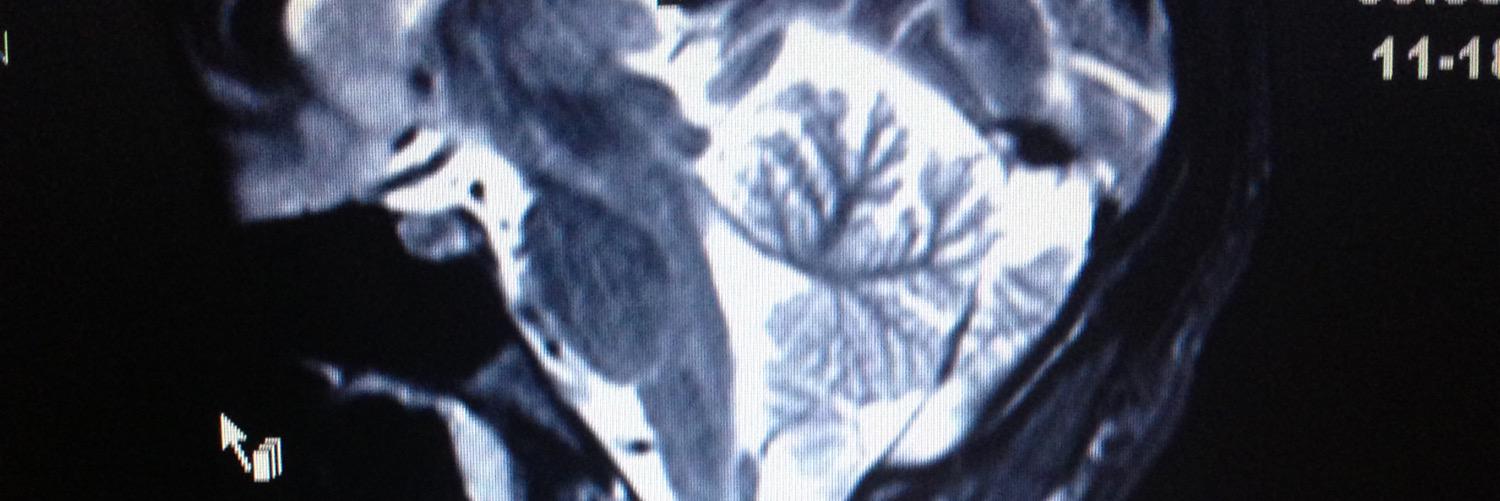

Topographical Model of #MS wins a Bronze at #CannesLions Health & Pharma. @SKriegerMD @harrisonandstar. Beyond Proud canneslionsarchive.com/winners/entry/…

six years to the day after the topographical model of #multiplesclerosis was presented at the #AANAM in 2015, she’s now officially “in the textbook.” still making the case that #MS is one disease yet unique in every person, here’s the original pub: nn.neurology.org/content/nnn/3/…